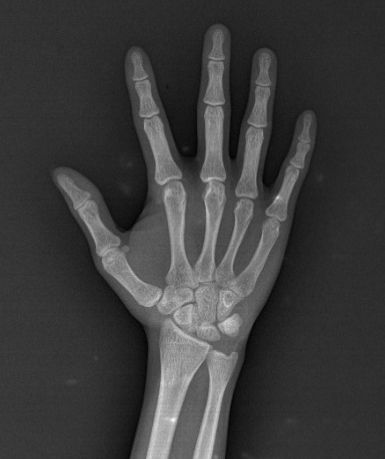

Tia X có khả năng xuyên qua nhiều loại mô, nhưng bị cản trở bởi các cấu trúc dày đặc như xương. Khi tia X đi qua cơ thể, chúng tạo ra hình ảnh với các mức độ tối sáng khác nhau trên phim hoặc màn hình, giúp các bác sĩ phát hiện gãy xương, tổn thương mô mềm, bệnh lý phổi, và nhiều vấn đề khác nhau.

Hình 1.2. Ảnh chụp X-quang tay